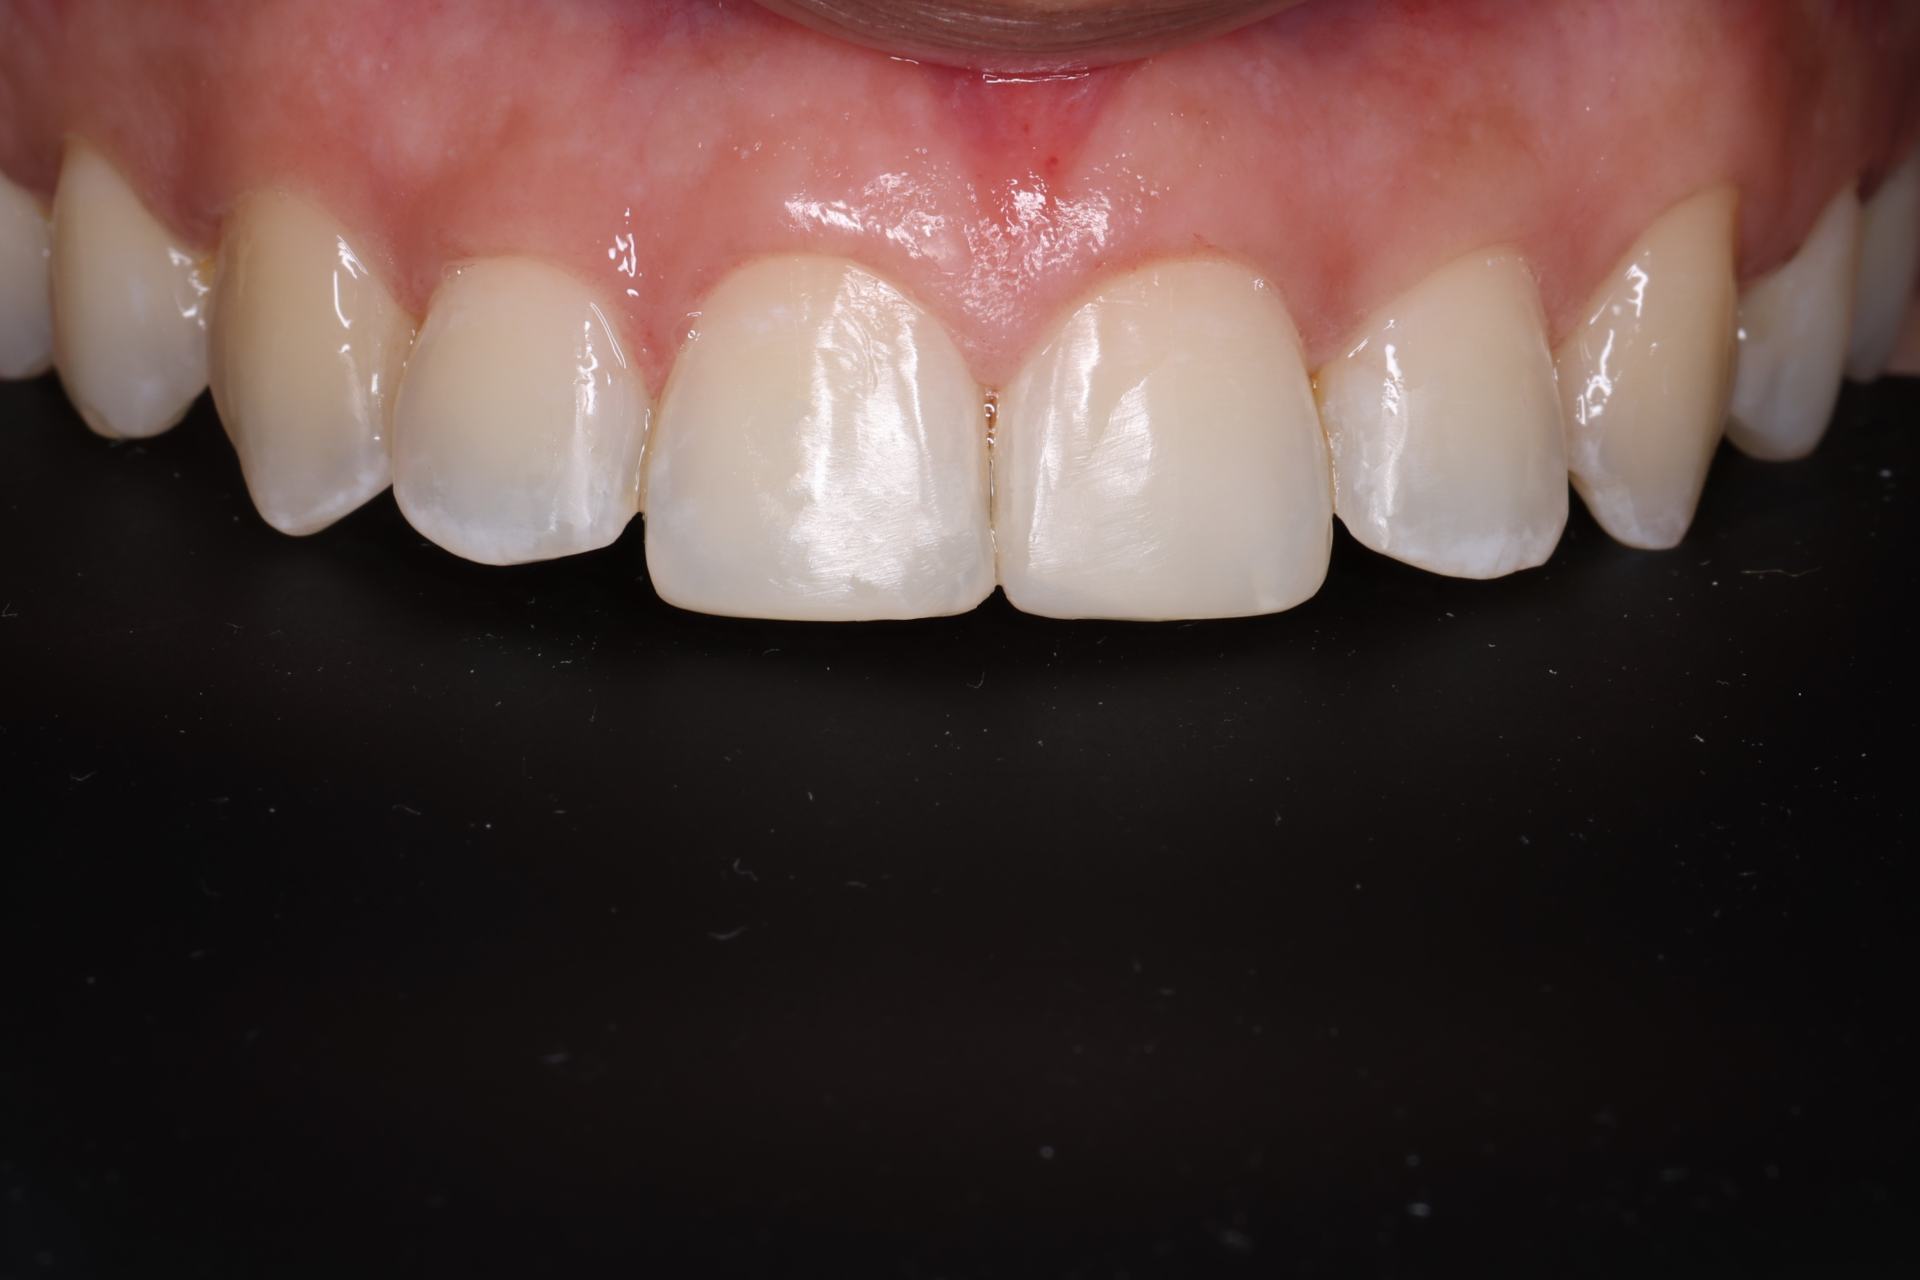

The tooth-coloured resin is applied in thin layers and shaped carefully to match natural anatomy. For front-tooth work, we may combine several shades for a lifelike result.

Aesthetic and Natural-Looking

The material matches your enamel, blending into the smile with virtually invisible transitions.